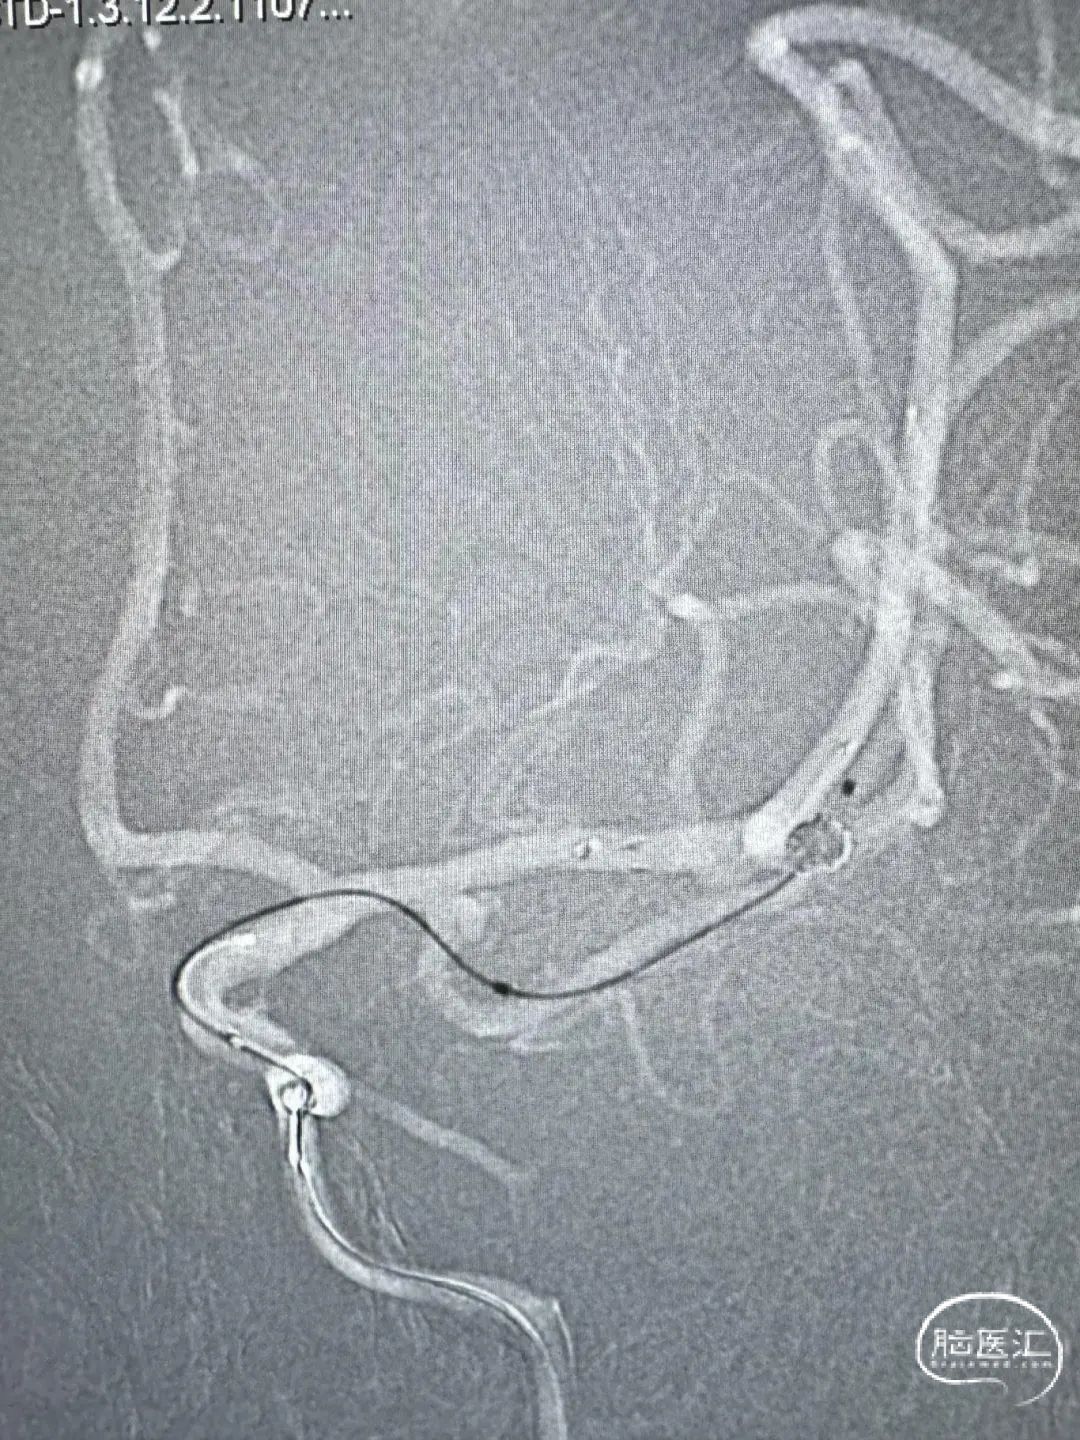

急诊头颅CTA:左侧大脑中动脉M1远端分叉处动脉瘤,左侧大脑中动脉M1段颞干分叉处动脉瘤。

左侧大脑中动脉M1段颞干分叉处动脉瘤

左侧大脑中动脉M1远端分叉处动脉瘤

两根Echelon-10分别备用支架及弹簧圈,首圈2.5mm×6cm(ev3)。

Atlas支架3mm×15mm,继续填圈1.5mm×4cm(Galaxy G3 MINI)及1.5mm×4cm(ev3)。

一根Echelon-10备选颞干,另一根Echelon-10送入瘤腔。

首圈1mm×3cm(ev3),最后用1mm×2cm(ev3)收尾。

术后正侧位造影。

动脉瘤完美栓塞,一个支架,两根微导管,一根微导丝主导全程,填塞致密。